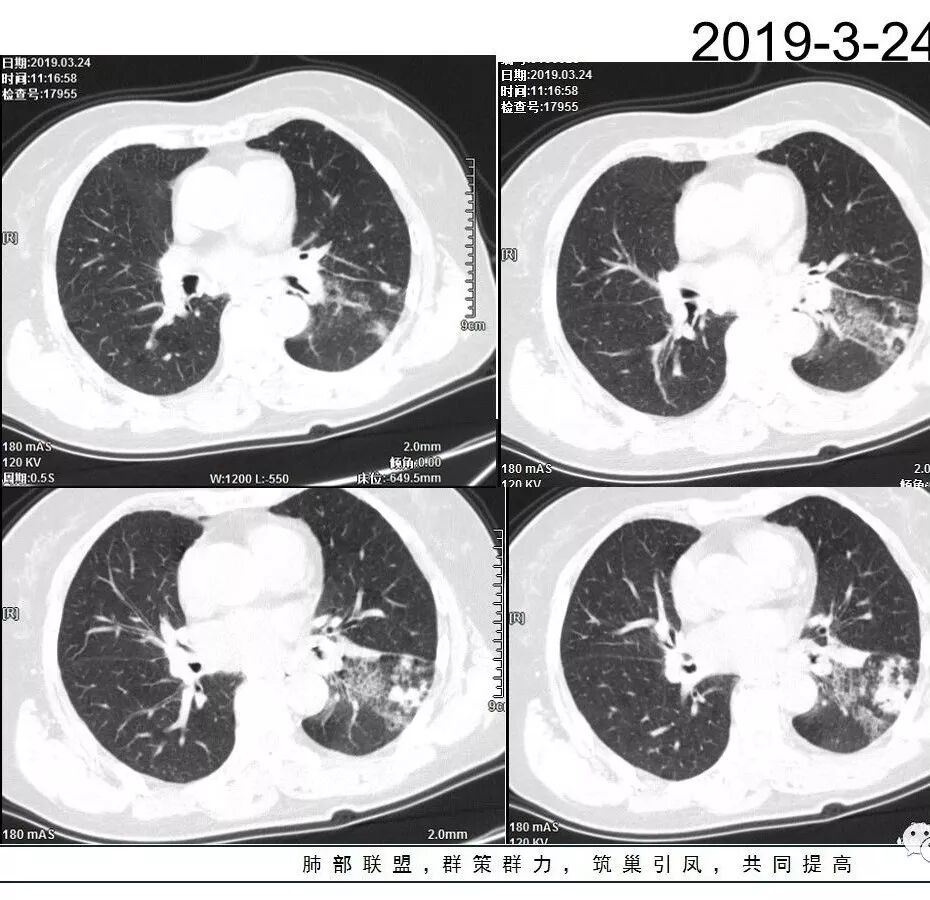

胸CT:左下叶实变影及磨玻璃影,小叶间隔增厚,内部支气管扩张、僵直。左肺门淋巴结肿大、钙化。考虑肺腺癌?合并感染

左肺下叶多发结节影及磨玻璃影,抗感染病灶部分吸收,增强扫描速升速降,左肺门见环形强化淋巴结,病灶反反复复,考虑肺炎型肺癌。

胸CT:左下叶基底段支气管狭窄,沿支气管分布斑片实变影、网格影、磨玻璃影,支气管充气征,无重力效应,左肺门淋巴结肿大、钙化。

左下叶实变影及磨玻璃影,内部支气管扩张、僵直。纵膈肺门淋巴结钙化。balf结核杆菌核酸阳性。

这三幅图是连续的,我们看到支气管中间这一幅狭窄了

大——小——大,狭窄后扩张

从这幅图看好像与周围病灶分界不清,支气管腔狭窄后扩张,支持炎性

今天这个病例有个明显的支气管狭窄,我倾向炎性,主要是和钙化淋巴结相关的,可能是继发的淀粉样变性。到底是什么感染,结核还是其他。我想看看复查后这个淋巴结,有没有突入到支气管腔内,如果有,他是继发于炎症的(比如中叶综合征,就是周围淋巴结压迫支气管,因为钙化淋巴结比较硬,支气管壁扛不住压力,突入支气管腔内,导致管腔狭窄,我们也称为结石征),如果没有,就和淋巴结关系不密切。之前有一例淀粉样变性的,淋巴结弥漫钙化,一种罕见的浆细胞型的CD。